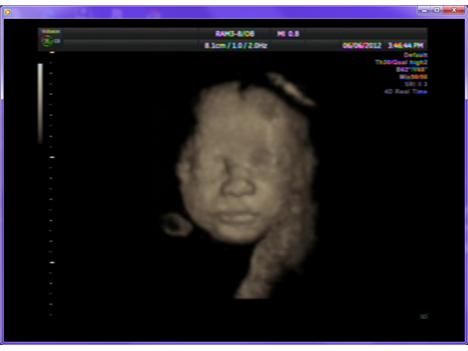

Byla jsem tento týden v Podolí na 3D ultrazvuku. Partner byl v zahraničí, tak jsem měla jako doprovod maminku a bráchu, kterého zajímala spíš technologie. Mamka byla celá natěšená na Kubíčka, říká si teď babča čekatelka. 😀 I druhá babička se už na našeho drobečka moc těší.

Náš mladý pán ale v čekárně na 3D záznam usnul, a tak když jsme přišli na řadu, pan doktor musel konstatovat, že spinká a je čelem k páteři, tj. přesně v pozici, kdy se záznam dělat nedá. Bylo mi doporučeno se projít, vyjít schody a víc se napít, aby se miminko probudilo a aktivovalo. Vzala jsem to po svém a schody jsem v Podolí z přízemí až do 4. patra zvládla hned několikrát, dala jsem si i pár dřepů a dostatečně se napila. Nechtěla jsem v čekárně strávit další hodinu a necítila jsem, že by se miminko výrazně vrtělo po mém rozcvičení. Když jsme ale přišli na ultrazvuk podruhé, pan doktor naopak konstatoval, že se Kubík hýbe až až! Máme několikaminutový záznam a fotečku obličeje.